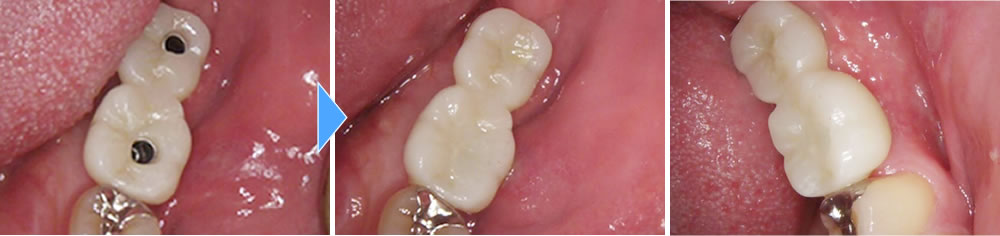

このオペが終わってから4ヶ月置き、しっかりと骨とインプラント体が結合している事を確認した後、上部の歯を作成していきました。

結果、綺麗な歯が出来上がりしっかりと噛む事ができるようになり、満足して頂く事ができました。